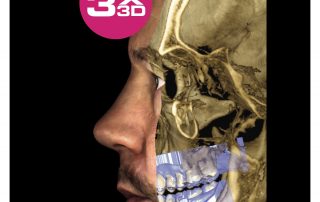

Planmeca ProMax 3D is a product family consisting of exceptional all-in-one units. All Planmeca CBCT units support three different types of 3D dental imaging – as well as panoramic, extraoral bitewing and cephalometric imaging. Planmeca is the first company to combine three different types of 3D data within one X-ray unit, ensuring these intelligent machines meet all maxillofacial imaging requirements. The ProMax family brings together a Cone Beam Computed Tomography (CBCT) image, 3D face photo and 3D model scan into one 3D image – using the same advanced software.